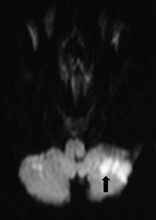

Claude综合征病灶模式图,病灶主要在红核下一个层面,累及小脑上脚,红核并非主要受累对象。(1为红核,2为小脑上脚,二者不在同一层面,2为主要受累部位,染为深色)

6个Claude综合征患者的病灶,显示病灶主要累及小脑下脚,有时可带一点红核。